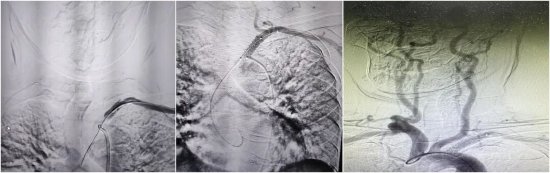

所谓“会师技术”,就像是在山体隧道挖掘中,从山的两端同时动工,在中间汇合。一方面,继续保留股动脉通路,从近心端进行“正向”试探;另一方面,在张女士左侧手腕处开辟第二条微创通道(桡动脉入路),从血管远端进行“逆向”进攻。能否在原本搏动微弱的桡动脉上穿刺成功是逆向通路建立成功的关键。在神经内科介入团队的努力下,成功穿刺左侧桡动脉,在DSA高清影像的引导下,逆向导丝犹如长了眼睛一般,缓慢且坚定地向前推进。终于,在反复调整角度和路径后,两根导丝在闭塞段内精准“会师”。随后,利用逆向导丝作为“生命线”,将正向球囊顺利送至病变部位,依次进行扩张。随着一枚支架精准释放在左锁骨下动脉开口处,血管瞬间被撑开。

术后即刻造影显示:闭塞的血管重新开通,血流畅通无阻,左侧椎动脉恢复了正向供血。原本摸不到的左侧脉搏、乃至远侧桡动脉也恢复了有力跳动。

(支架顺利植入左锁骨下动脉开口处,造影提示左侧椎动脉正向血流恢复)